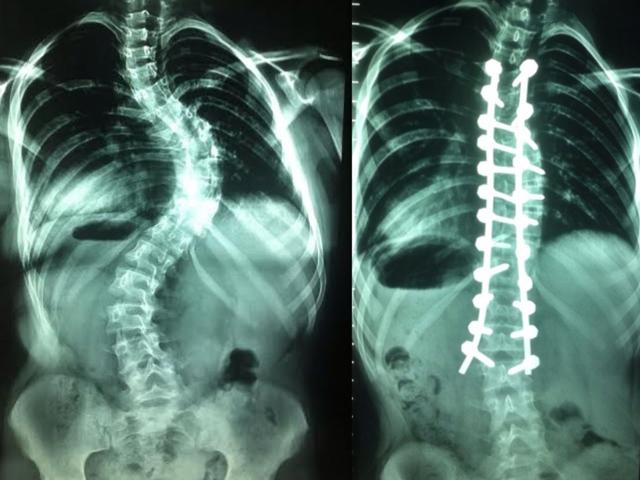

Una niña de 12 años presentaba una malformación de la columna, de hasta en 72 grados, el cual ponía en riesgo su vida y, por ende, su movilidad. Sin embargo, gracias a un minucioso trabajo de especialistas del Departamento de Traumatología del Hospital Guillermo Almenara de EsSalud se pudo corregir esta imperfección implantando 23 tornillos con barras de titanium.

“Se trata de un caso muy delicado, ya que poco a poco la deformación podía generar una disfunción respiratoria, cardiaca y que podía derivar en la muerte del paciente. Sin embargo, han sido 8 horas de arduo trabajo que nos han permitido salvar la vida de la paciente”, explicó Héctor Zegarra, jefe del Departamento de Traumatología.